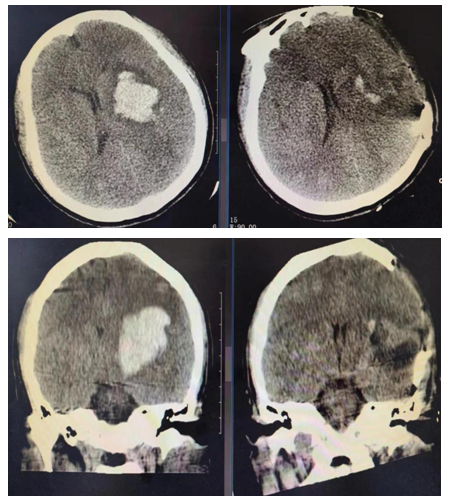

患者为44岁女性,因“突发意识不清7小时”入院。来院后行颅脑CT平扫示左侧基底节区脑出血,量约42ml。患者意识呈浅昏迷,颅内出血量大、血肿位置较深、中线偏移明显。根据临床表现,行全面检查,并充分评估,患者行神经内镜手术指征明确,无禁忌症。李帅医生于当天夜里第一时间紧急指导县医院神经外科团队为患者在全麻下行神经内镜辅助下颅内血肿清除术。手术过程顺利,术后患者生命体征平稳,复查颅脑CT平扫可见血肿清除满意,止血良好。